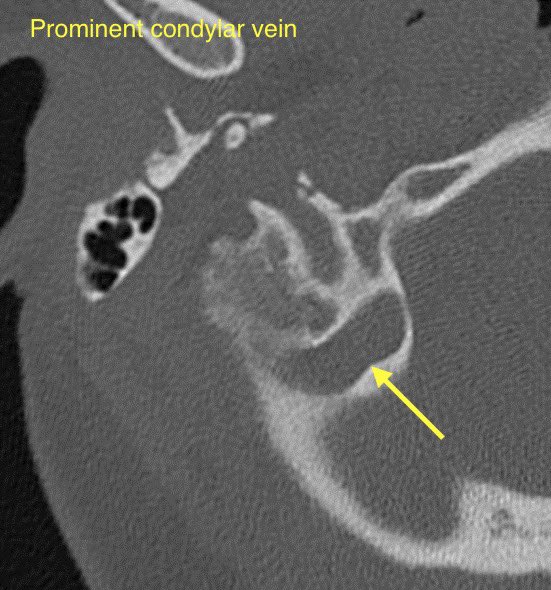

🔷EMISSARY VEIN ANOMALIES AND VARIANTS

1️⃣Mastoid emissary veins

2️⃣Condylar veins

3️⃣Petrosquamosal emissary veins

🔹Mastoid emissary veins (connect posterior auricular or occipital veins with the sigmoid sinus). These are common & usually incidental findings though have been associated with PT

🔹Condylar veins are anastomotic emissary veins that connect the distal sigmoid sinuses or proximal jugular veins with the suboccipital and deep cervical venous plexus

🔹These are often observed incidentally though have been associated with PT